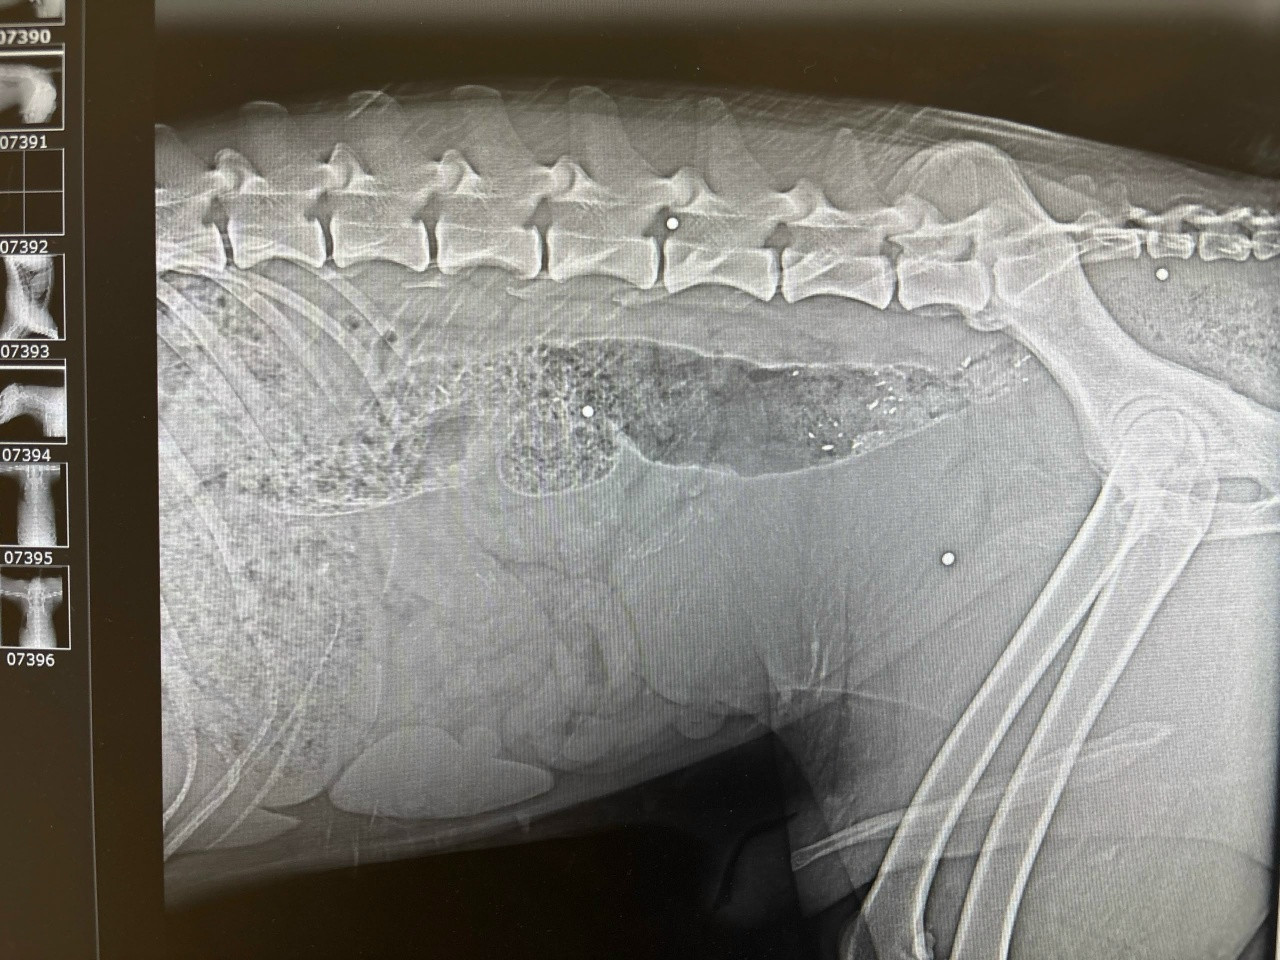

Как сообщили в выборгском паблике помощи животным, 25 апреля в поселке Приветнинское из оврага у реки Приветной подняли кобеля со следами ранений дробью. Рентген показал присутствие металла в позвоночнике. Собака несколько дней лежала на берегу.